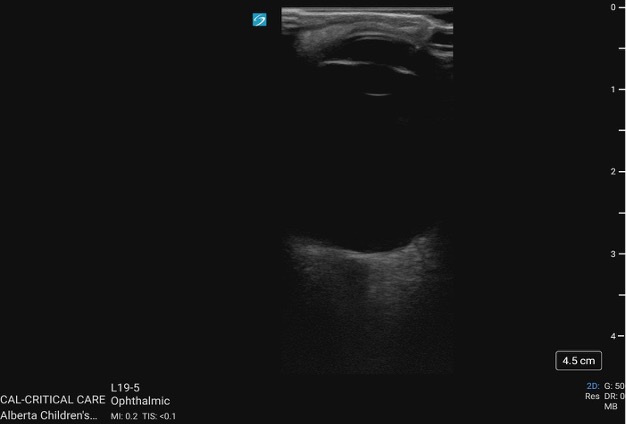

The contraction of the LV occurs in a complex but coordinated manner, combining longitudinal shortening, radial thickening, and circumferential constriction [20]. The base of the heart moves toward the apex as the ventricle shortens, while the cavity simultaneously decreases in diameter due to inward wall motion. This multidirectional contraction pattern efficiently ejects blood into the aorta and gives the ventricle its characteristic torsional motion, where the apex rotates slightly counterclockwise and the base clockwise during systole [20].

In normal systolic function, the LV walls should thicken visibly and move inward symmetrically, coming close to one another during systole. All walls should demonstrate coordinated inward motion and uniform thickening (radial contraction). You should also see the base move toward the apex (longitudinal shortening). Although circumferential shortening contributes to the overall narrowing of the cavity, this is not directly distinguishable on standard PoCUS imaging.

Figure 2a. Normal function seen in the A4C view